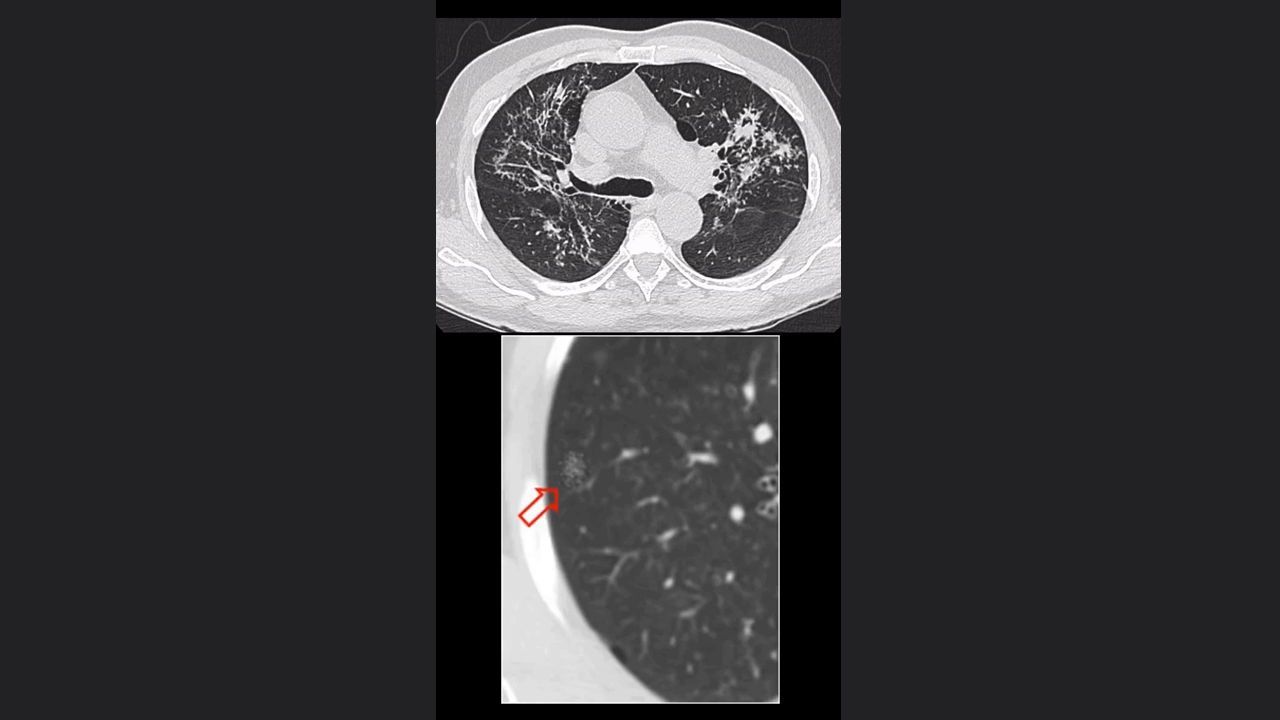

Nódulos

Características del EPOC